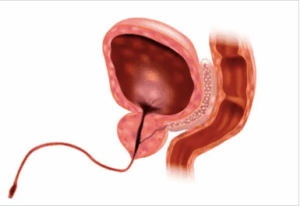

Inability to urinate, or urinary retention, is a medical emergency. The most common cause of urinary retention in men, is BPH. The prostate grows to the point of preventing any urine from passing through. If your prostate is preventing you from urinating, you need it treated sooner rather than later.